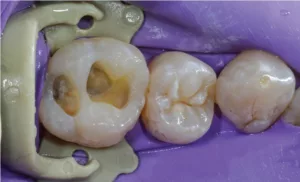

Dr. Mennito True Dental Dam article isolation FIGURE 2

The “soft” clamps are made from a material called PEEK (polyether ether ketone). What I love about them is that they are much kinder to the tissue and, therefore, more comfortable for the patient than those metal clamps we all struggled with in dental school. Our practice is all about the patient experience, and I don’t want to have to give palatal injections to put a dam on. The good news is that with these, I rarely have to, and I can use them for 90%+ of my cases.